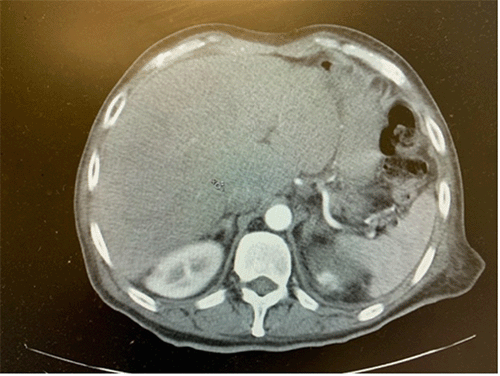

Computed Tomography (CT) of the chest, abdomen, and pelvis demonstrated gastric wall pneumatosis with associated extensive portal venous gas, complex air-filled lesions within the left hepatic lobe, and mild pneumoperitoneum. These findings were highly concerning for emphysematous gastritis, potentially with perforation (Figure 1). The patient was initiated on broad-spectrum intravenous antibiotics (piperacillin-tazobactam) and aggressively resuscitated with lactated Ringer’s solution.

Figure 1. Initial Computed Tomography Findings of Emphysematous Gastritis and its Sequelae. Published with Permission.

Axial contrast-enhanced CT scan of the abdomen on presentation. The image demonstrates extensive portal venous gas (PVG, purple arrow), gas collections within the left hepatic lobe (blue arrows) consistent with hepatic involvement, and extraluminal free air (pneumoperitoneum, green arrow), collectively indicative of severe emphysematous gastritis with associated complications